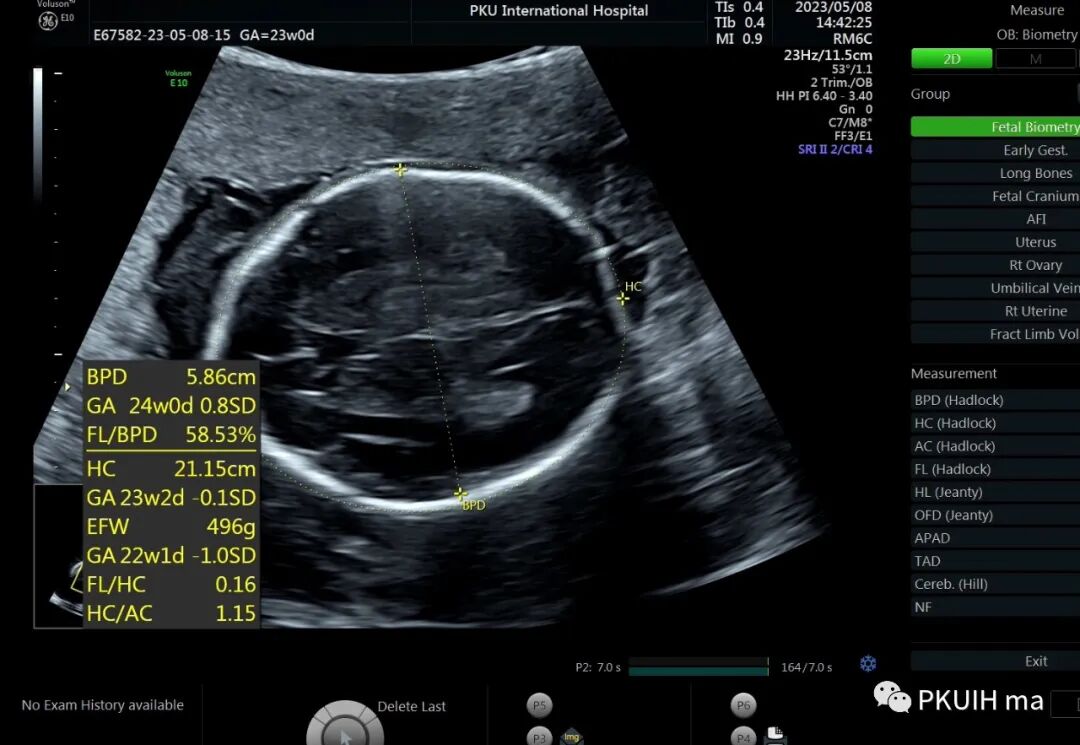

孕23周常规筛畸发现四肢长骨偏短,孕妇月经正常,核对早孕超声,孕周也没问题。

双顶径及头围正常,骨骼回声强度没有发现异常。